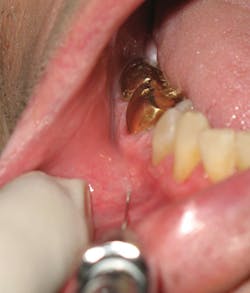

6. With the bevel oriented toward the bone, insert the needle at the depth of the mucobuccal fold usually at the canine or first premolar. Resting the syringe barrel on the finger providing retraction assists in stabilization (see Figure 5).

7. Advance, slowly, toward the foramen (see Figure 6), approximately 5-6 mm; aspirate in two planes. Avoid contact with bone.

Figure 5: Insertion and stabilization

Figure 6: Angulation and target